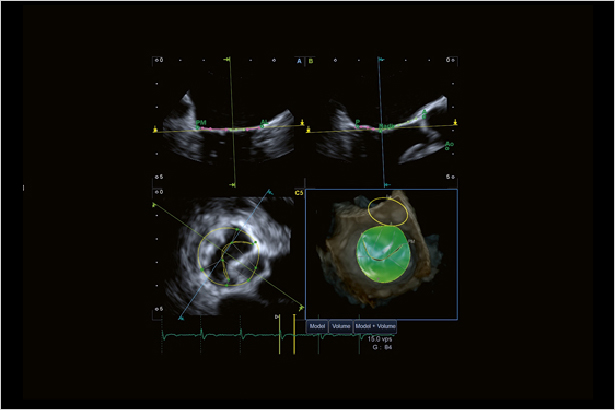

自動化的MVA工具提供精準的二尖瓣解剖和功能評估。該功能的四幅顯示可以從不同掃描平面提供清晰的視角。